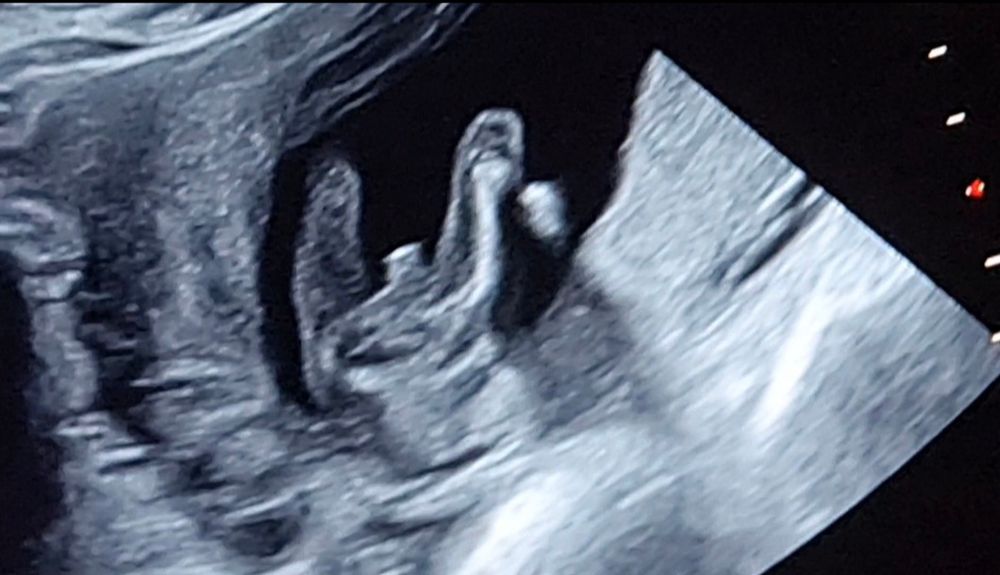

на узи все было неплохо видно, однако у мужа страх, что бубенцы испаряться. Вот хотелось бы вашего мнения

Хорошие такие уже бубенчики с писюнчиком видны, сомневаюсь, что это пуповина😅

наш писюн, на таком сроке все уже видно, пусть желание сбудется:)